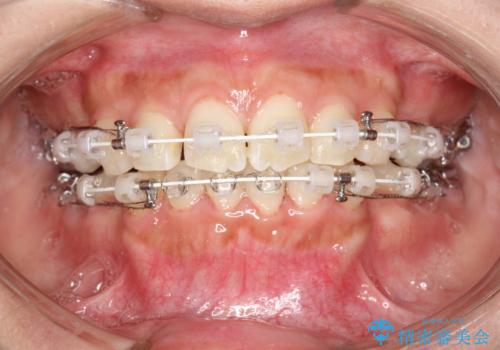

- 審美装置

- 口元が出てるのが気になるとのことで来院されました。

上下左右前から4番目の歯を抜歯して前歯を後方に下げて、口元を下げる計画としました。

口元を大きく改善したい場合は抜歯が必要となることが多いです。